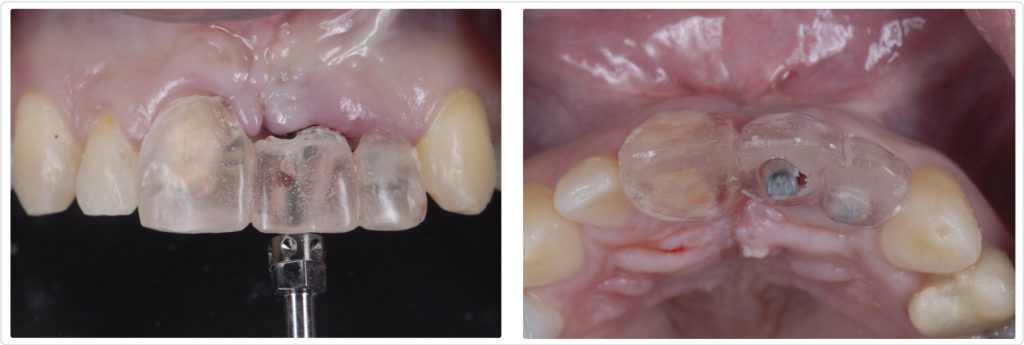

The orthodontic therapy (Figs. 9 and 10) took nearly a year, and luckily the patient adhered to our recommendations and home care (which can be problematic with some patients). Once the ortho was finalized, we extracted the lateral incisor, placed two osseointegrated implants using a restrictive surgical template, and then restored them (Figs. 11 and 12).

While the esthetic outcome (Figs. 13 and 14) wasn’t 100% perfect, our team provided a very reasonable result, particularly when considering how the patient initially presented.